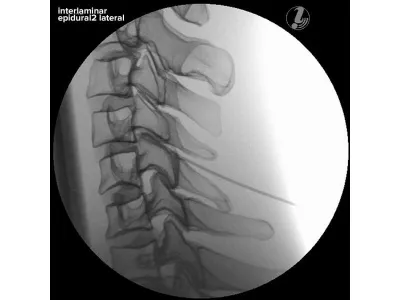

Тренажер для спинальной анестезии

Тренажер для спинальной анестезии (или эпидуральной анестезии) используется для обучения и тренировки медицинских специалистов, таких как анестезиологи и акушеры-гинекологи, в проведении данных процедур.

- Тренажер медицинский для анестезиологии и реаниматологии представляет собой модель нижней части торса человека, точно имитирующую анатомию поясничной области с костными ориентирами, позволяющую как измерять, так и забирать спинномозговую жидкость в реалистичных условиях

- Обеспечивает точные ощущения сопротивления кожи и подлежащих структур при продвижении люмбальной иглы

- В тренажере для отработки инъекций имеется анатомическая модель поясничного отдела позвоночника для более подробного изучения анатомии